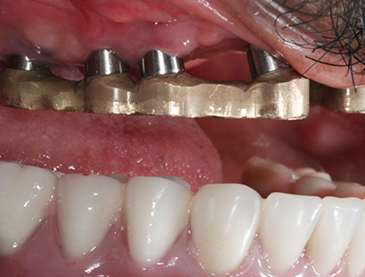

Fully edentulous clinical cases